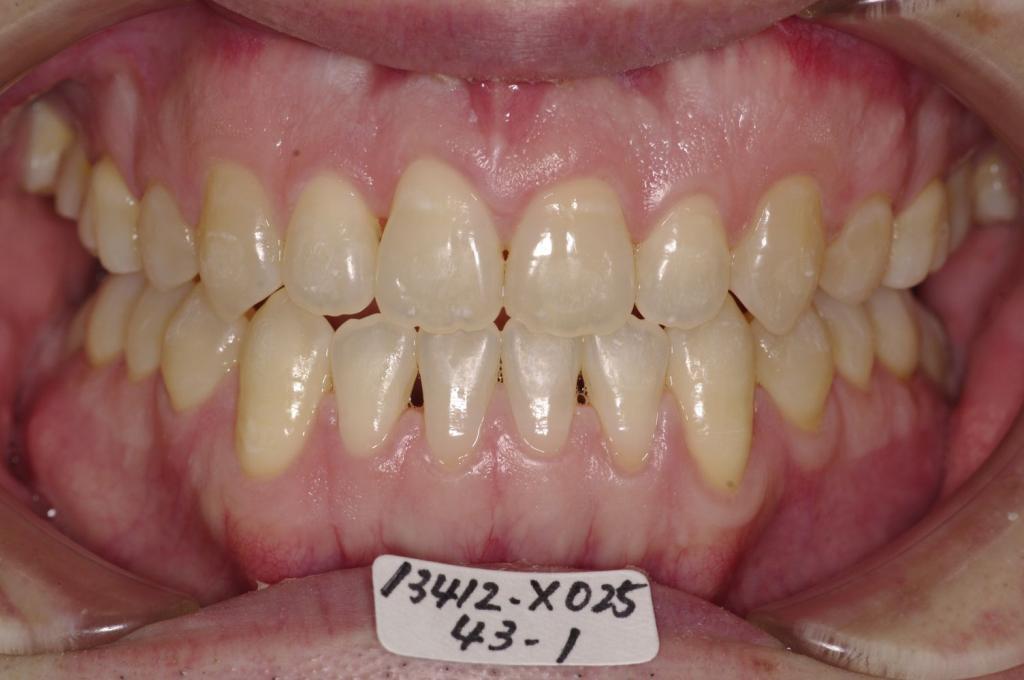

顎、顔の歪みの矯正治療

(治療期間、治療前後写真、治療方法、費用)WORKS